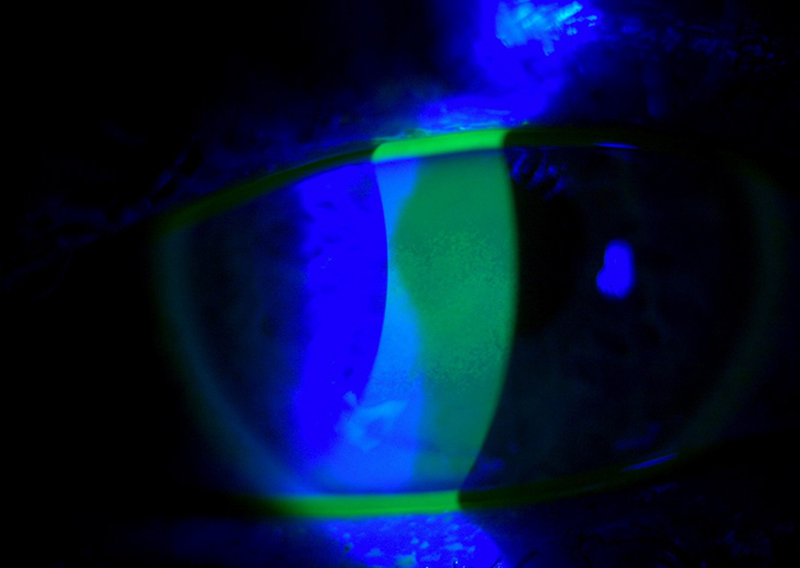

- Slit Lamp Exam